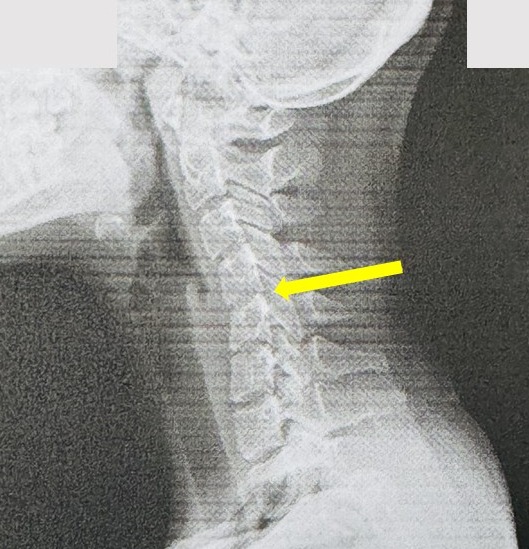

【X光片下的證據:被「滑」掉的生命曲線】

健康的頸椎,從側面看,天生就帶有一個優美的「C字形」向前弧度。這個弧度是上帝賜予的天然避震器,用來支撐頭顱的重量、緩衝日常活動的壓力。然而,請看左圖這位20歲女孩的頸椎,那條生命曲線已經消失,變成一條令人擔憂的僵硬直線!這就是「手機頸」或「軍人頸」,是頸椎結構提早退化的鐵證。